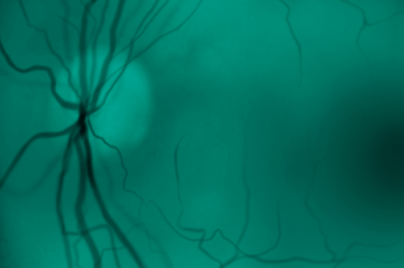

Our eyes have a blood-retinal barrier that protects our delicate retinal tissue. When the barrier is compromised, fluid can leak into the macula – the central part of the retina responsible for sharp, detailed vision – and other areas of the eye, causing swelling that can lead to vision loss for people living with DME and wet AMD.

NOTE: These images are diagrammatic representations of the eye for illustrative purposes only.